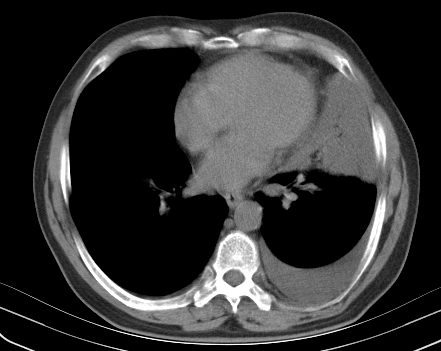

以下是引用老爱克斯新网客在2008-7-31 6:30:00的发言:[br]左肺上叶大片状病灶,左肺上叶支气管狭窄呈鼠尾状,左肺门增大,纵隔内见肿大淋巴结,左侧胸腔积液,余肺清晰。左肺中心型肺癌淋巴结转移,

以下是引用zjb在2008-7-31 6:32:00的发言:[br]左侧中心性肺癌 阻塞性肺炎 肺不张 胸腔积液 建议气管镜

以下是引用zjzjr在2008-7-31 8:45:00的发言:[br]考虑左侧中心性肺癌伴阻塞性肺炎,左肺上叶肺不张,纵隔淋巴结转移;左侧胸腔积液。建议行纤支镜检查。

以下是引用sdzyy在2008-7-31 8:47:00的发言:[br]病灶较治疗前有所进展,胸水增多, 左侧中心性肺癌 并 阻塞性肺炎 肺不张 胸腔积液 可能性大; 建议气管镜检查。 [br] [br]